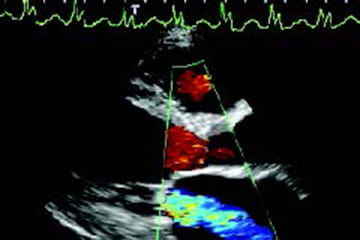

Echocardiography Concentration

Students who enroll in the echocardiography concentration learn to create images of the heart and vascular system. Generally, these sonographers are employed in the cardiology department within the hospital, outpatient centers and physician offices. Some echocardiographers perform some vascular examinations, as well. Students learn the examinations echocardiographers perform. Further specialization in the last two semesters of the program is available for students who desire to concentrate on either adult echocardiography or pediatric echocardiography. Types of exams students learn:

- Adult cardiac

- Pediatric cardiac

- Stress Echocardiography

- Assist in cardiac procedures

- Assist in Transesophogeal echocardiography

- Vascular exams